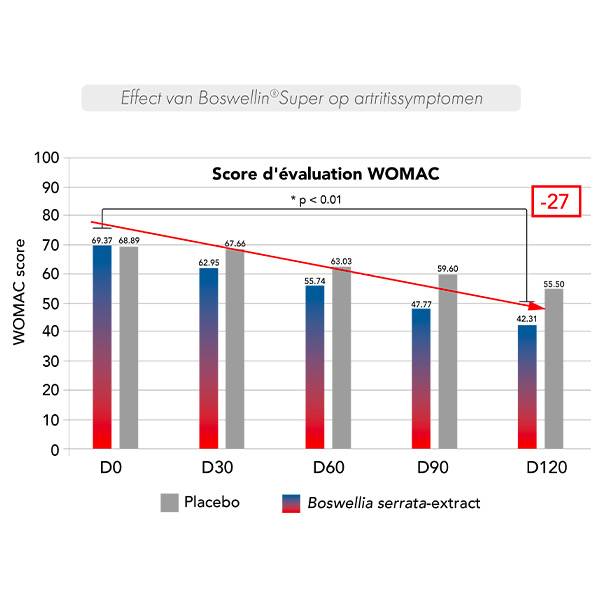

Een dubbelblind, placebogecontroleerd klinisch onderzoek bij 48 personen met de diagnose artrose in de knie werd gedurende 120 dagen uitgevoerd.

Symptomen geassocieerd met artrose werden beoordeeld met behulp van een deelnemersvragenlijst (WOMAC**).

De artritissymptomen namen geleidelijk af van 30 dagen tot 120 dagen.

**WOMAC (Western Ontario and Mc Master Universities Arthritis Index) mesure la douleur articulaire et la fonction articulaire dans la vie quotidienne.